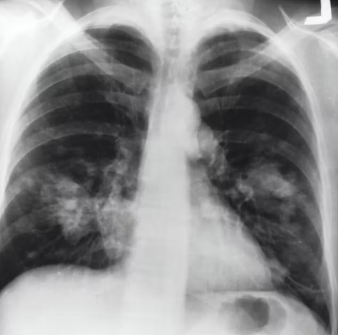

천식의 약물 치료는 증상 완화와 폐 기능 유지, 급성 악화 방지를 목표로 합니다. 크게 증상 완화제와 질병 조절제로 나뉩니다. 증상 완화제로는 속효성 기관지 확장제(SABA)를 사용하여 급성 천식 발작 시 숨 가쁨을 빠르게 해소합니다.

질병 조절제는 만성적인 기관지 염증을 조절하는 약제로, 흡입 스테로이드(ICS)가 가장 중요하며, 지속성 베타-2 효능제(LABA)나 류코트리엔 조절제(LTRA) 등을 병용하기도 합니다. 약물은 의사의 처방에 따라 정해진 용법과 용량을 지켜 꾸준히 복용하고, 올바른 흡입기 사용법을 숙지하는 것이 중요합니다.

대부분의 천식은 약물 및 비약물 치료로 조절되지만, 약물 치료에도 반응하지 않는 심한 천식 환자의 경우 기관지 열 성형술과 같은 시술을 고려할 수 있습니다. 이는 기관지 내부의 두꺼워진 평활근에 열을 가하여 이완시켜 기관지 협착을 줄이는 시술입니다.

천식 치료 분야에서는 기존 치료에 반응하지 않는 중증 천식 환자를 위한 생물학적 제제(Biologics)의 개발 및 적용이 활발합니다. 항-IgE 항체(오말리주맙), 항-IL-5/IL-5R 항체(메폴리주맙, 레슬리주맙, 벤랄리주맙), 항-IL-4R 알파 항체(듀피젠트) 등이 있으며, 개인의 천식 유형(알레르기성, 호산구성)에 따라 맞춤형으로 사용됩니다.